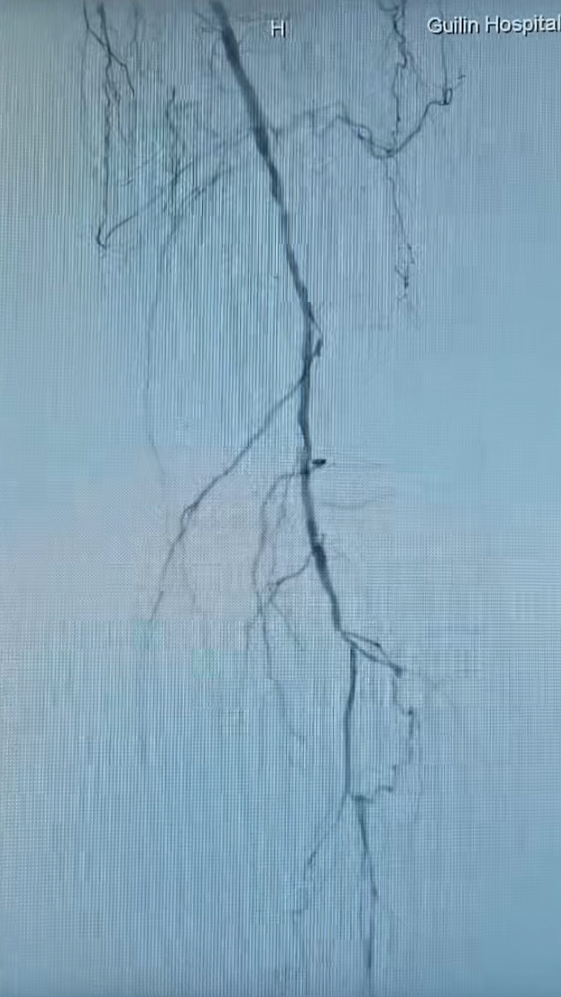

术前足.png

术后足.png

足部动脉的术前(左)术后(右)影像对比